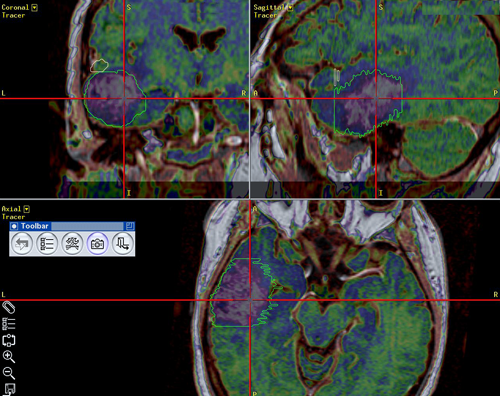

Navi5

Νευροπλοήγηση σε ασθενή με κροταφικό όγκο εγκεφάλου. Ο όγκος με πράσινο περίγραμμα, η άνω κροταφική έλικα που πρέπει να διατηρηθεί με ρόζ περίγραμμα.